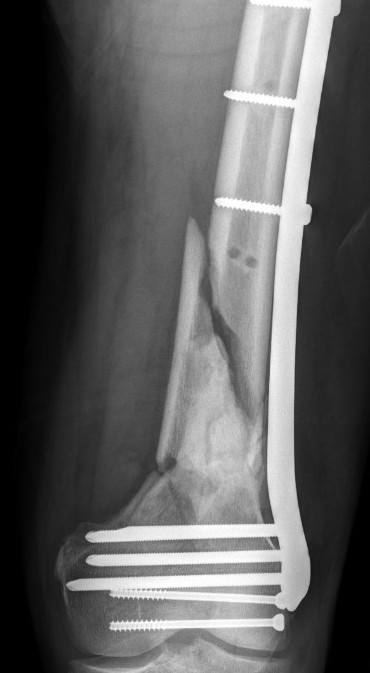

Type C: Complete articular

Xray / CT

Options

Dual Plate

Plate + Retrograde nail

Distal femur replacement

Indications

Significant comminution

Loss of medial cortical buttress

Results

- 21 comminuted distal femur fractures

- increased union rates with double v single plate

- increased revision rate with single plate